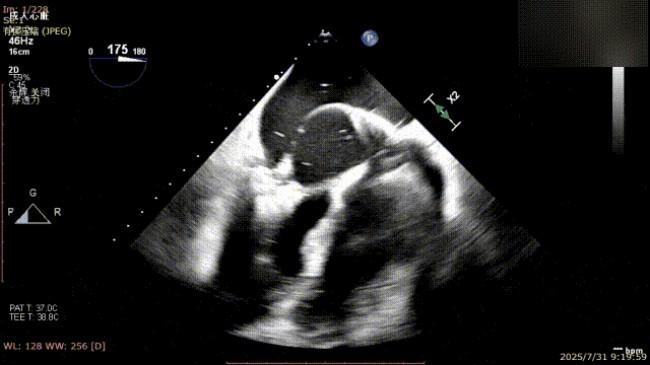

手术过程中,麻醉与围术期医学科副主任医师马金本确保麻醉过程平稳。心脏大血管外科主治医师董明亮穿刺股静脉置入血管鞘,并在心脏超声科梁皓主任及段福建教授TEE引导下,顺利穿刺房间隔,房间隔穿刺高度4.9cm。随后,在王安彪主任以及刘洋教授指导、心脏超声科梁皓主任TEE引导下,董明亮医师沿输送系统将延展呈“一字型”状态的国产夹合器送至左房,缓慢关闭夹合器并进行弹道测试。调整夹合器位置和方向后,董明亮医师再次将夹合器延展呈“一字型”完成跨瓣,避免发生腱索缠绕,成功捕获瓣叶后关闭夹合器,二尖瓣反流显著下降。夹合器完全解离后,超声示二尖瓣反流程度显著下降,残余反流0,平均跨瓣压差1mmHg,手术圆满成功。

捕获瓣叶并放下Gripper

关闭夹合器

解离前三维